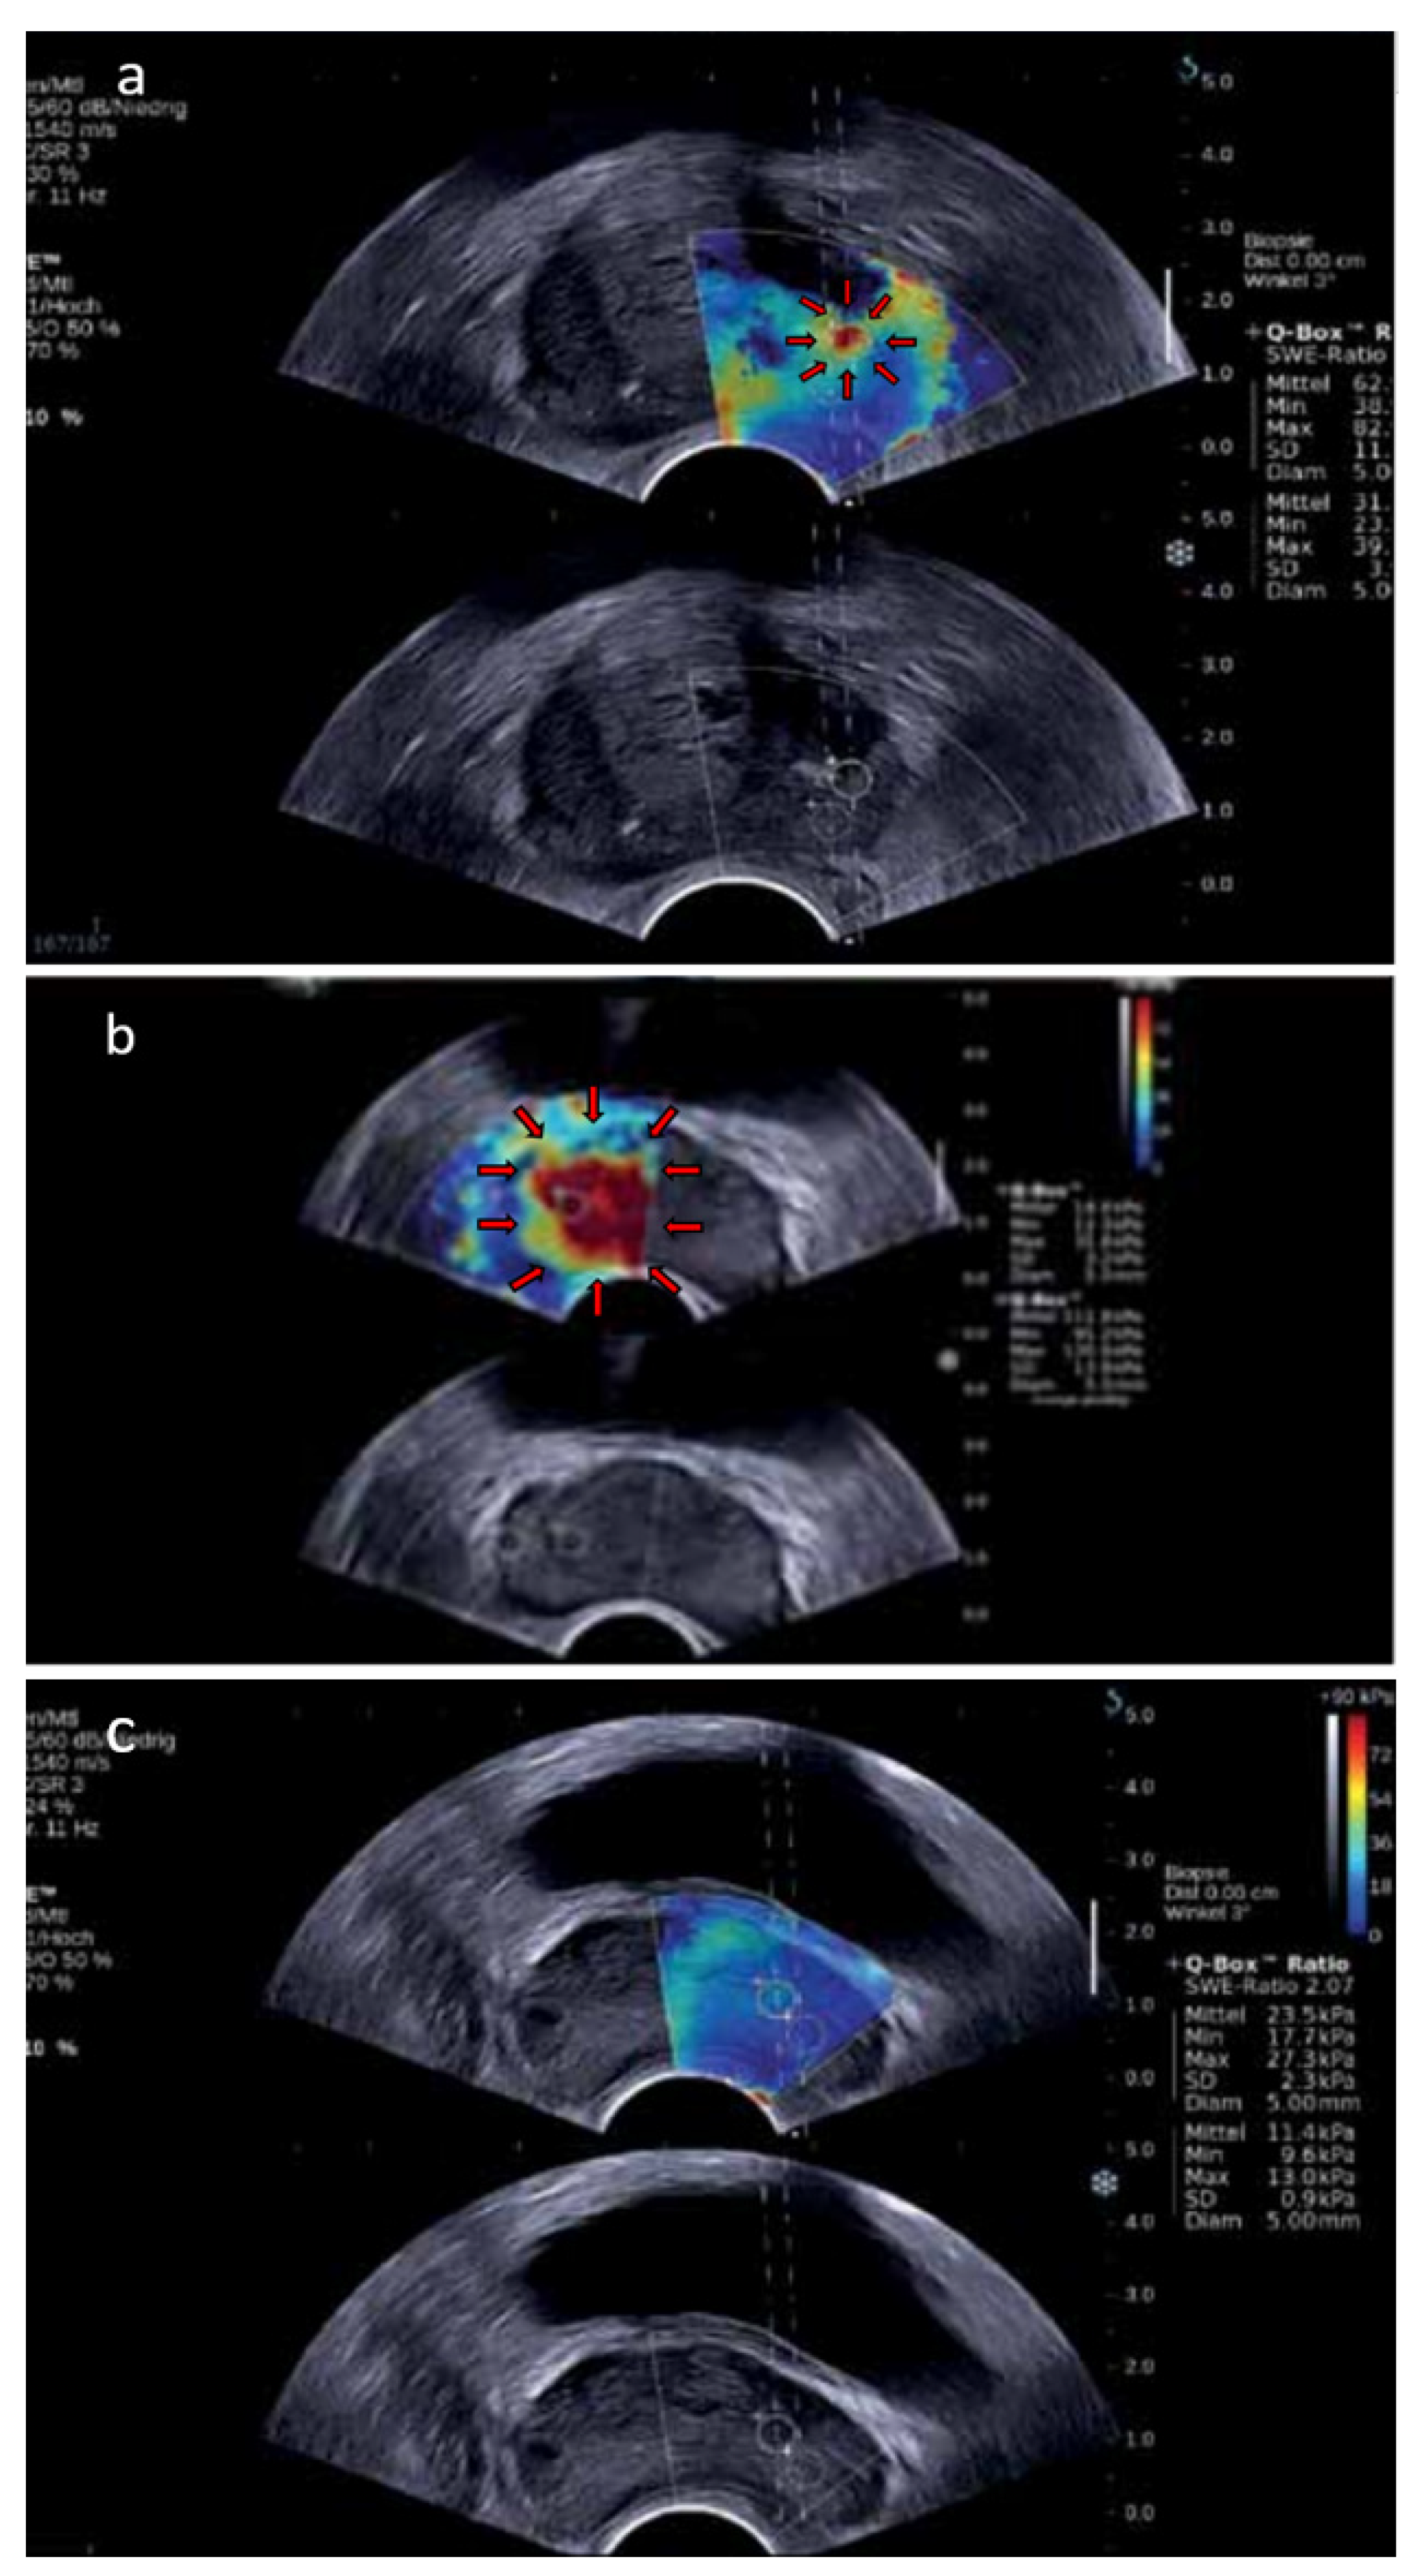

4.3. Shear-Wave Elastography

4.4. Multiparametric Ultrasound

- Barr, R.G.; Cosgrove, D.; Brock, M.; Cantisani, V.; Correas, J.M.; Postema, A.W.; Salomon, G.; Tsutsumi, M.; Xu, H.X.; Dietrich, C.F. WFUMB Guidelines and Recommendations on the Clinical Use of Ultrasound Elastography: Part 5. Prostate. Ultrasound Med. Biol. 2016, 43, 27–48. [Google Scholar] [CrossRef] [PubMed]

- Boehm, K.; Salomon, G.; Beyer, B.; Schiffmann, J.; Simonis, K.; Graefen, M.; Budaeus, L. Shear Wave Elastography for Localization of Prostate Cancer Lesions and Assessment of Elasticity Thresholds: Implications for Targeted Biopsies and Active Surveillance Protocols. J. Urol. 2015, 193, 794–800. [Google Scholar] [CrossRef] [PubMed]

- Rouvière, O.; Melodelima, C.; Hoang Dinh, A.; Bratan, F.; Pagnoux, G.; Sanzalone, T.; Crouzet, S.; Colombel, M.; Mège-Lechevallier, F.; Souchon, R. Stiffness of Benign and Malignant Prostate Tissue Measured by Shear-Wave Elastography: A Preliminary Study. Eur. Radiol. 2016, 27, 1858–1866. [Google Scholar] [CrossRef]

- Correas, J.M.; Tissier, A.M.; Khairoune, A.; Vassiliu, V.; Méjean, A.; Hélénon, O.; Memo, R.; Barr, R.G. Prostate Cancer: Diagnostic Performance of Real-Time Shear-Wave Elastography. Radiology 2015, 275, 280–289. [Google Scholar] [CrossRef] [PubMed]

- Ji, Y.; Ruan, L.; Ren, W.; Dun, G.; Liu, J.; Zhang, Y.; Wan, Q. Stiffness of Prostate Gland Measured by Transrectal Real-Time Shear Wave Elastography for Detection of Prostate Cancer: A Feasibility Study. Br. J. Radiol. 2019, 92, 20180970. [Google Scholar] [CrossRef] [PubMed]